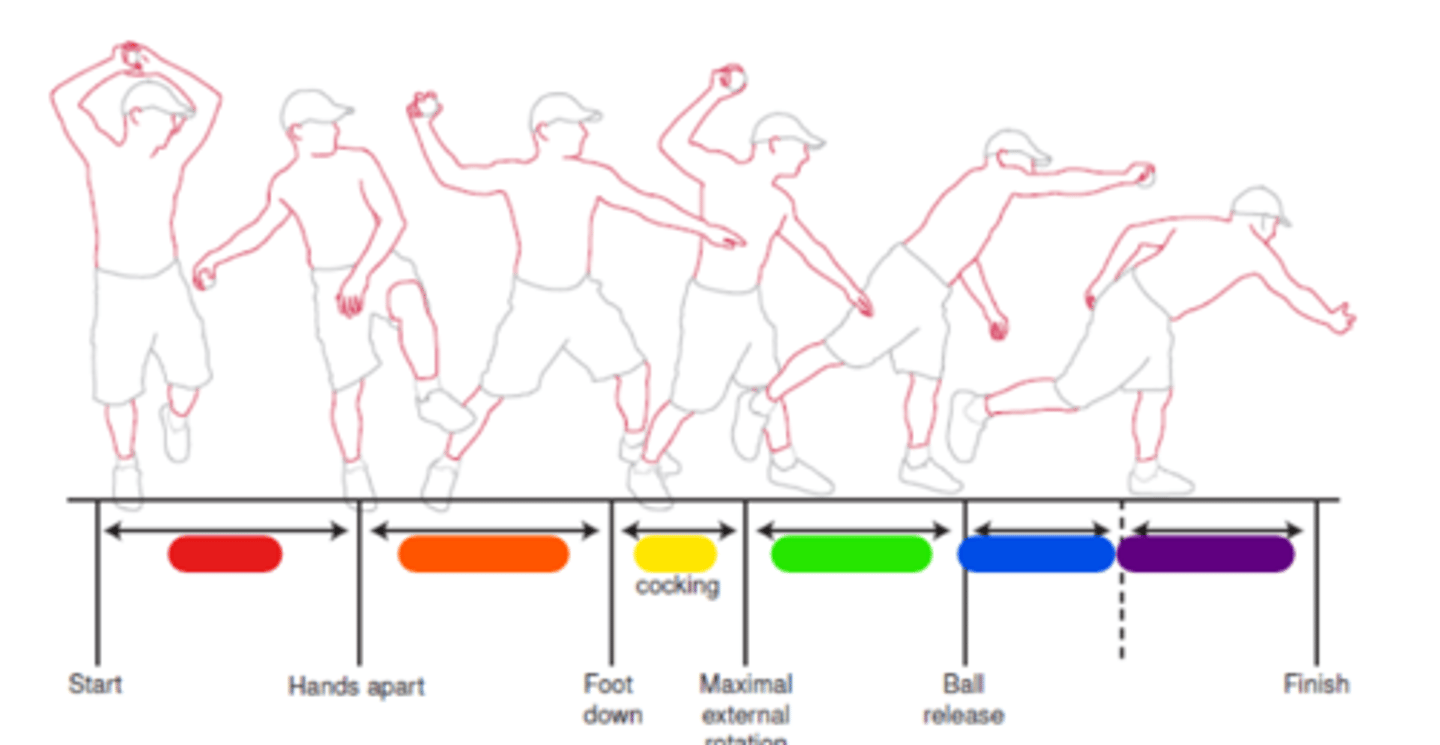

Windup

Red in image.

Early cocking

Orange in image.

Late cocking

Yellow in image.

Acceleration

Green in image.

Deceleration

Blue in image.

Follow through

Purple in image.